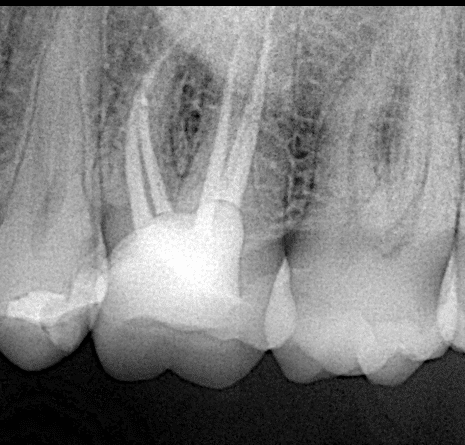

Preoperative x ray

Final x ray , look to the fitness of the lithium disilicate on the biobase